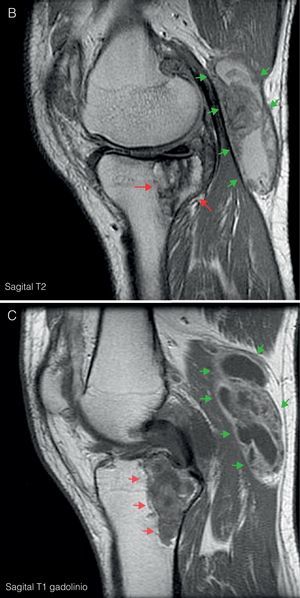

Ante las lesiones radiológicas de la rodilla izquierda, se completó el estudio con una RM de rodilla izquierda (fig. 3) en la que se objetivó proliferación sinovial difusa hipointensa en T1, con erosiones óseas en el margen posterolateral del cóndilo femoral. Un gran quiste de Baker con zonas de alta y baja señal en T2. y lesión lítica hipointensa en T1, con señal heterogénea en T2 a nivel de la epífisis proximal tibial con un diámetro máximo de 5cm, que tras administración de gadolinio mostraba realce, imagen característica de depósitos tofáceos.

A) RM de rodilla izquierda corte coronal en T1. Muestra proliferación sinovial difusa hipointensa, con erosiones óseas en el margen posterolateral del cóndilo femoral (flecha azul) y en escotadura intercondílea. Lesión lítica hipointensa en epífisis proximal tibial con un diámetro máximo de 5cm (flechas rojas). B) Corte sagital en T2. Se observa un aumento heterogéneo de señal a nivel de la lesión lítica en epífisis tibial (flechas rojas); junto con un gran quiste de Baker situado por detrás del vientre muscular del gemelo interno (flechas verdes), con zonas de alta y baja señal, correspondientes a hipertrofia sinovial. C) Corte sagital en T1 con Gd. Tras la administración de gadolinio se objetiva realce periférico a nivel de la lesión lítica tibial (flechas rojas) y del quiste de Baker (flechas verdes).